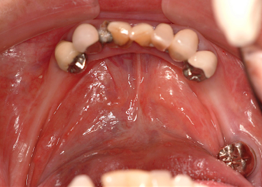

治療対象は、無歯顎(全く歯が無い方)、または残存歯がほとんど良くない方です

3.インプラントの本数を少なくできることは、経済的も優れています。従来の治療では、無歯はでは10〜14本のインプラントを埋入していたのでそれと比較すると、かなりの治療費を削減できると考えます。